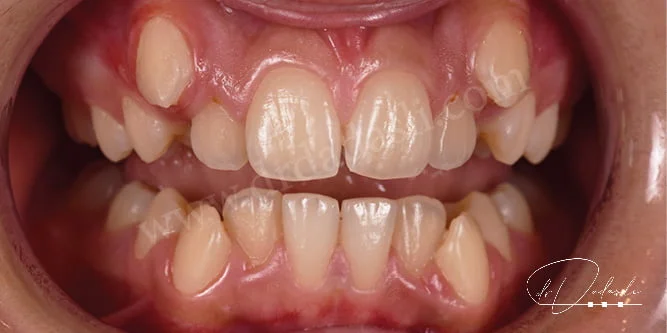

- Açık kapanış (Şekil 5 ve 6) – ağız kapatıldığı zaman alt ve üst ön dişler arasında boşluk kalmasıdır. Bazı olgularda arka taraftaki dişler arasında da açık kapanış olabilir.